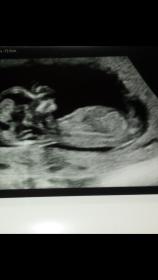

I think girl

Guessing girl too:)